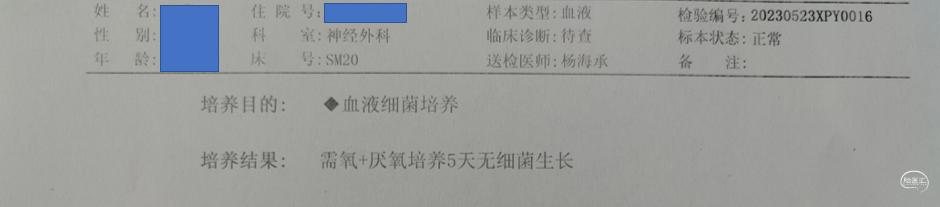

入院检查

入院化验

积极纠正凝血功能:氨甲环酸1g